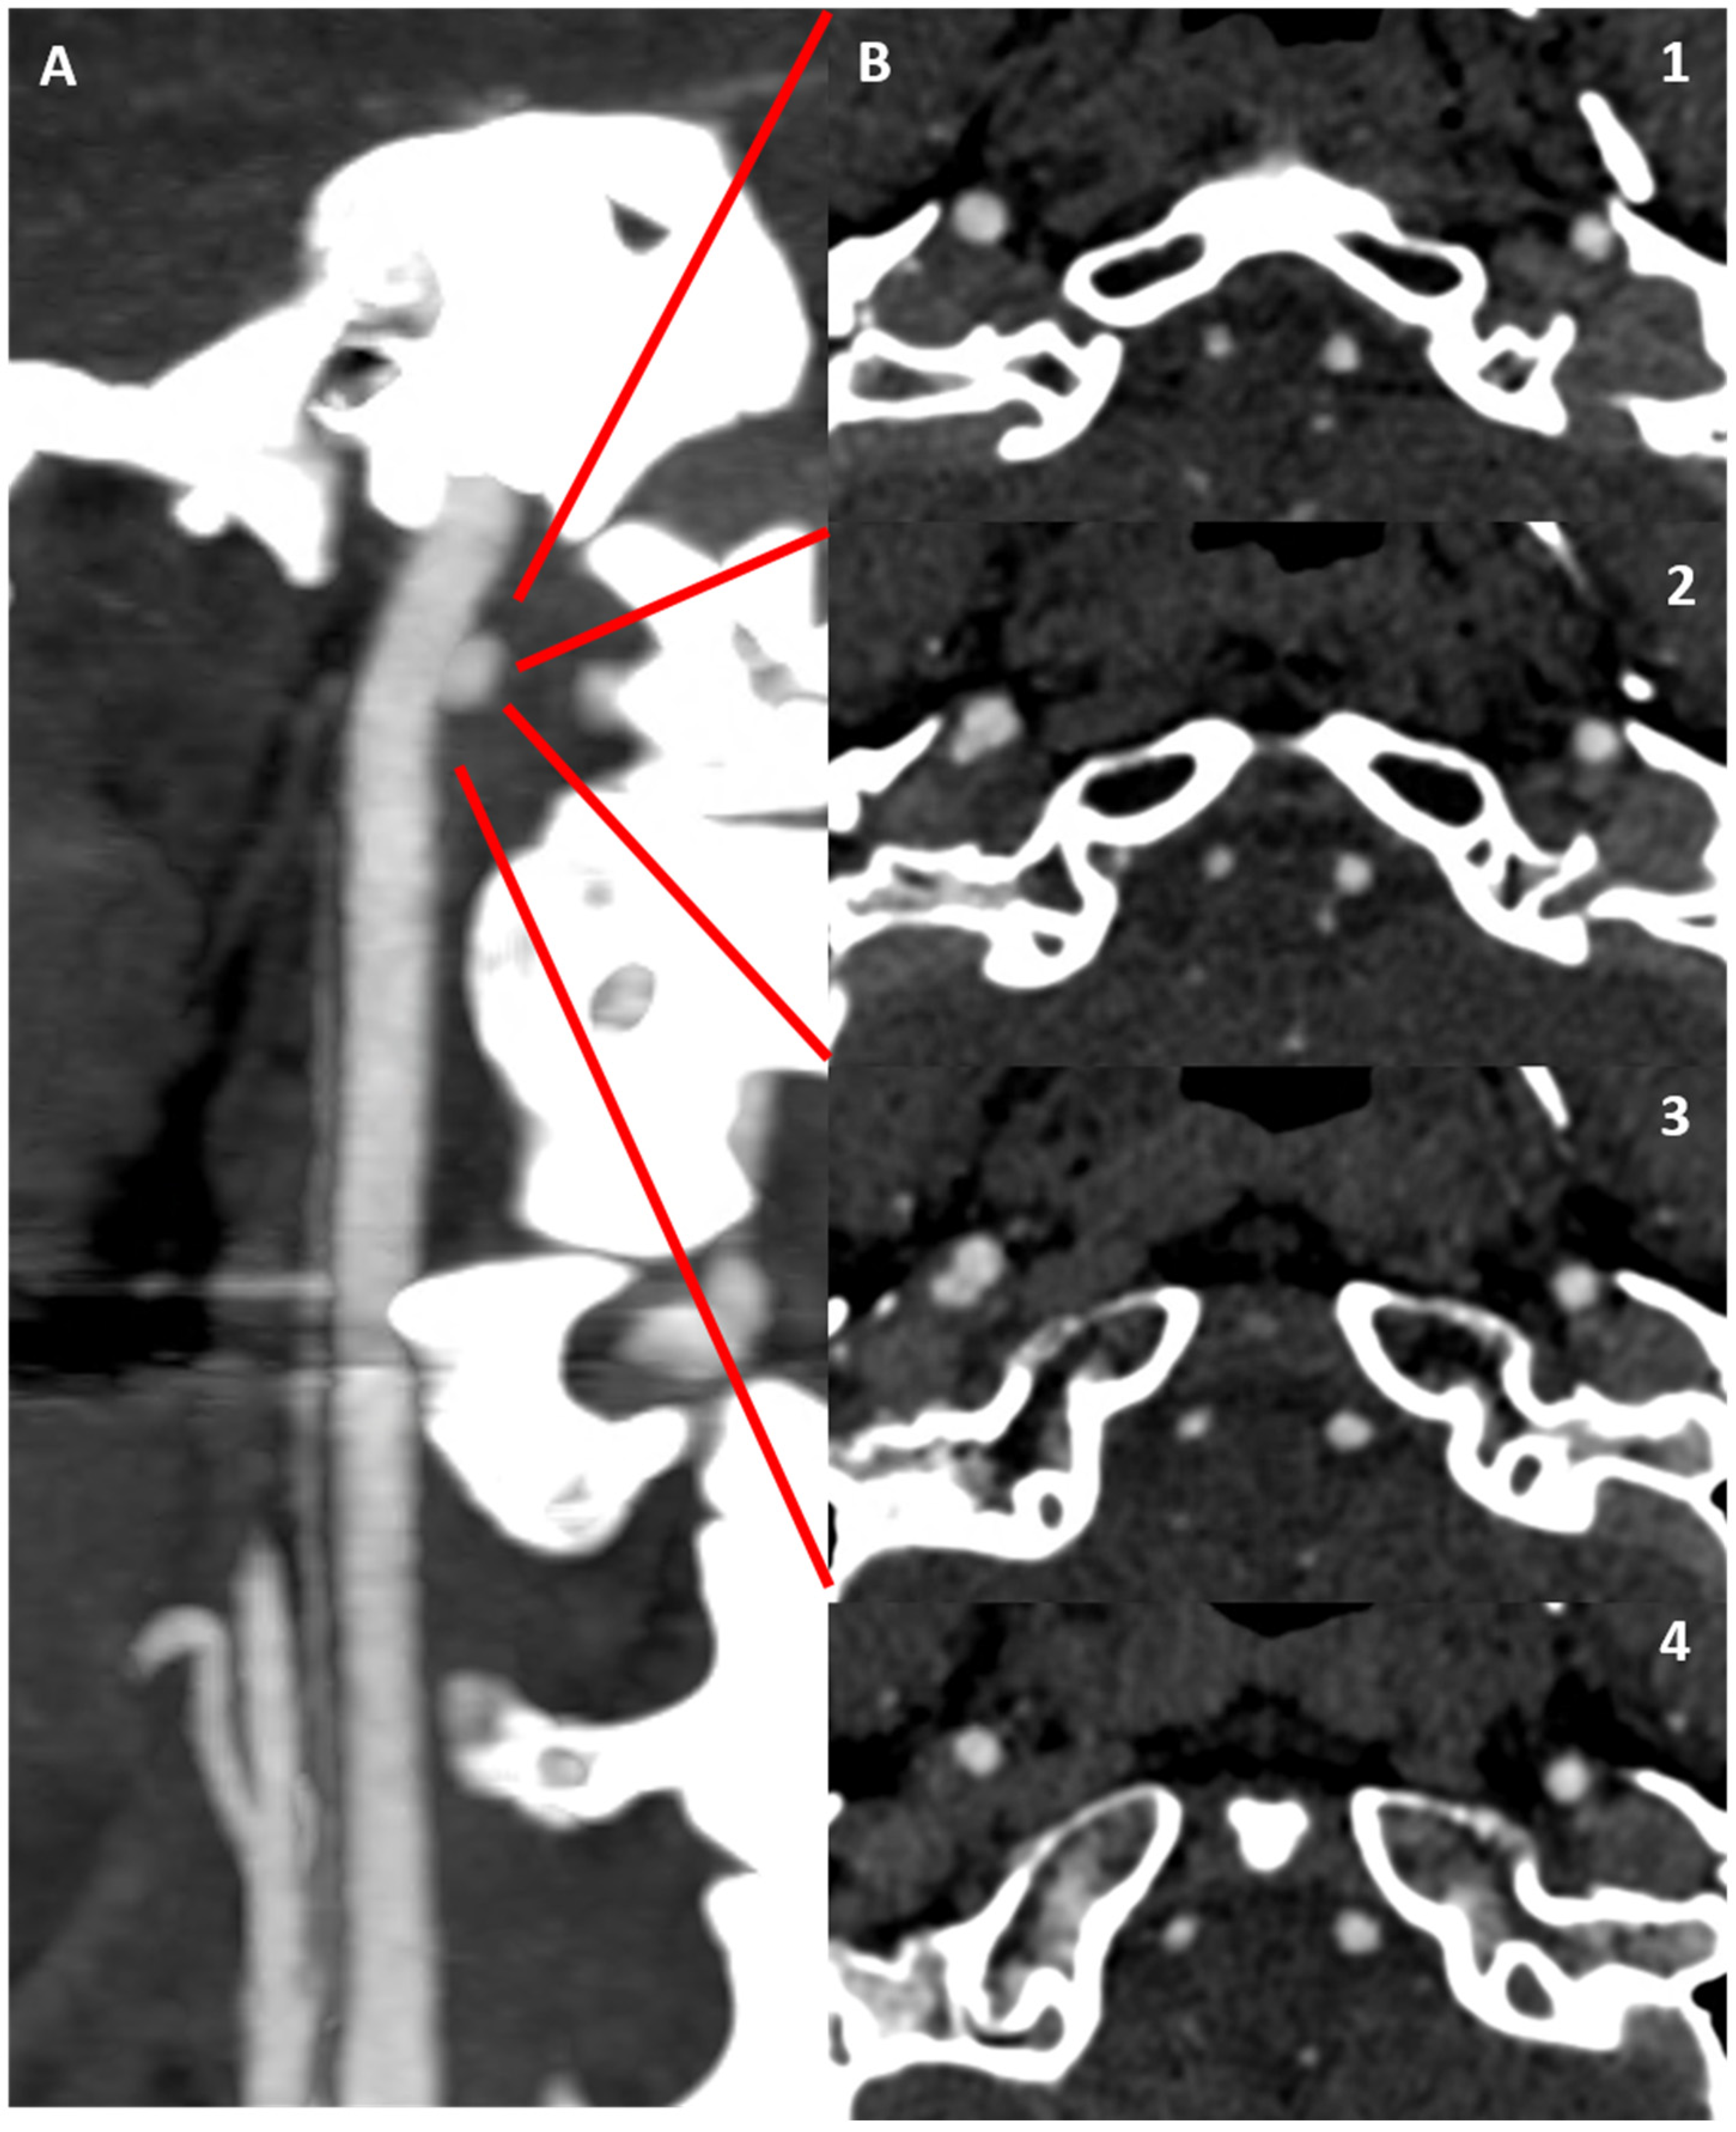

3.1. Case 1